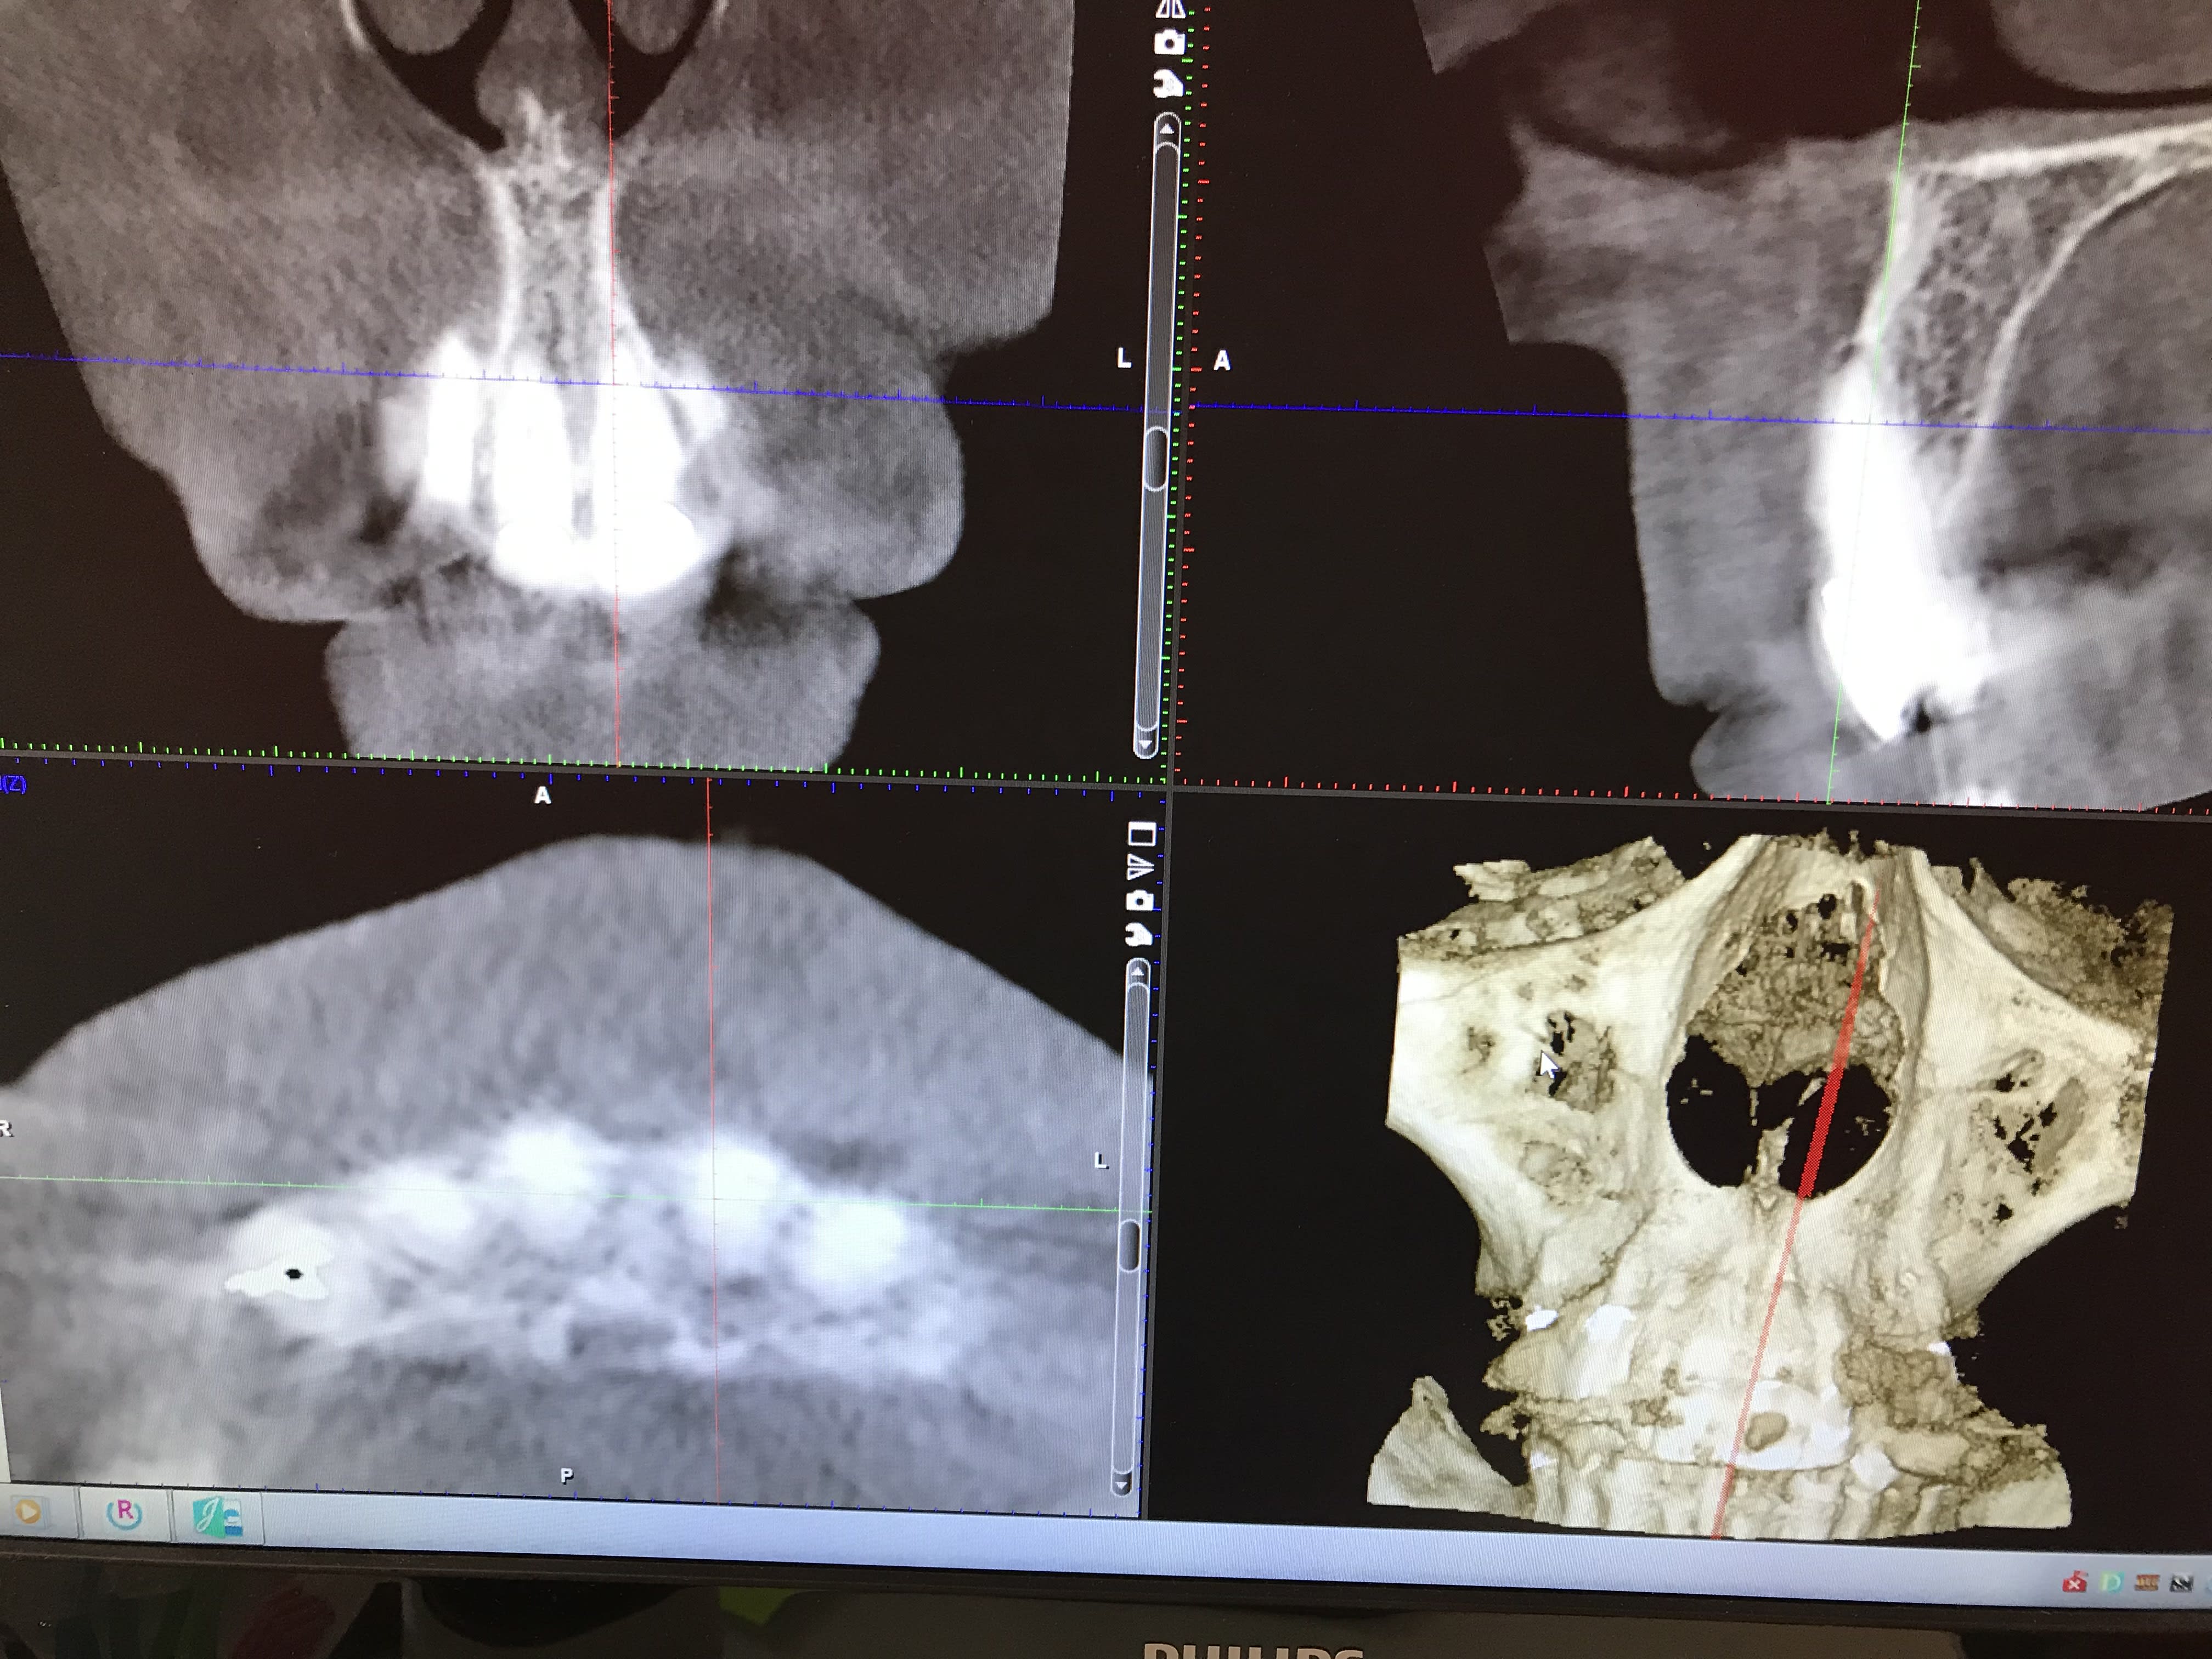

Patiente avec pilier de bridge 13 fracturé + 15 paro mobile + 25 paro mobile + 22 légèrement mobile. Les seules dents "viables" sur l'arcade sont 11, 21 et 22 et la 12 a été extraite entre temps.

Sur les coupes conebeam, très peu d'os au niveau de 13 et surtout 14 en épaisseur, un peu plus au niveau de 23 et 24 et pas assez d'os au niveau de 15 et 25 (présence des sinus).

Posit peut gérer aussi le sourire gingival ? Je veux dire simuler l’ ostéoplastie nécessaire avant pose des implants et bridge prov ?